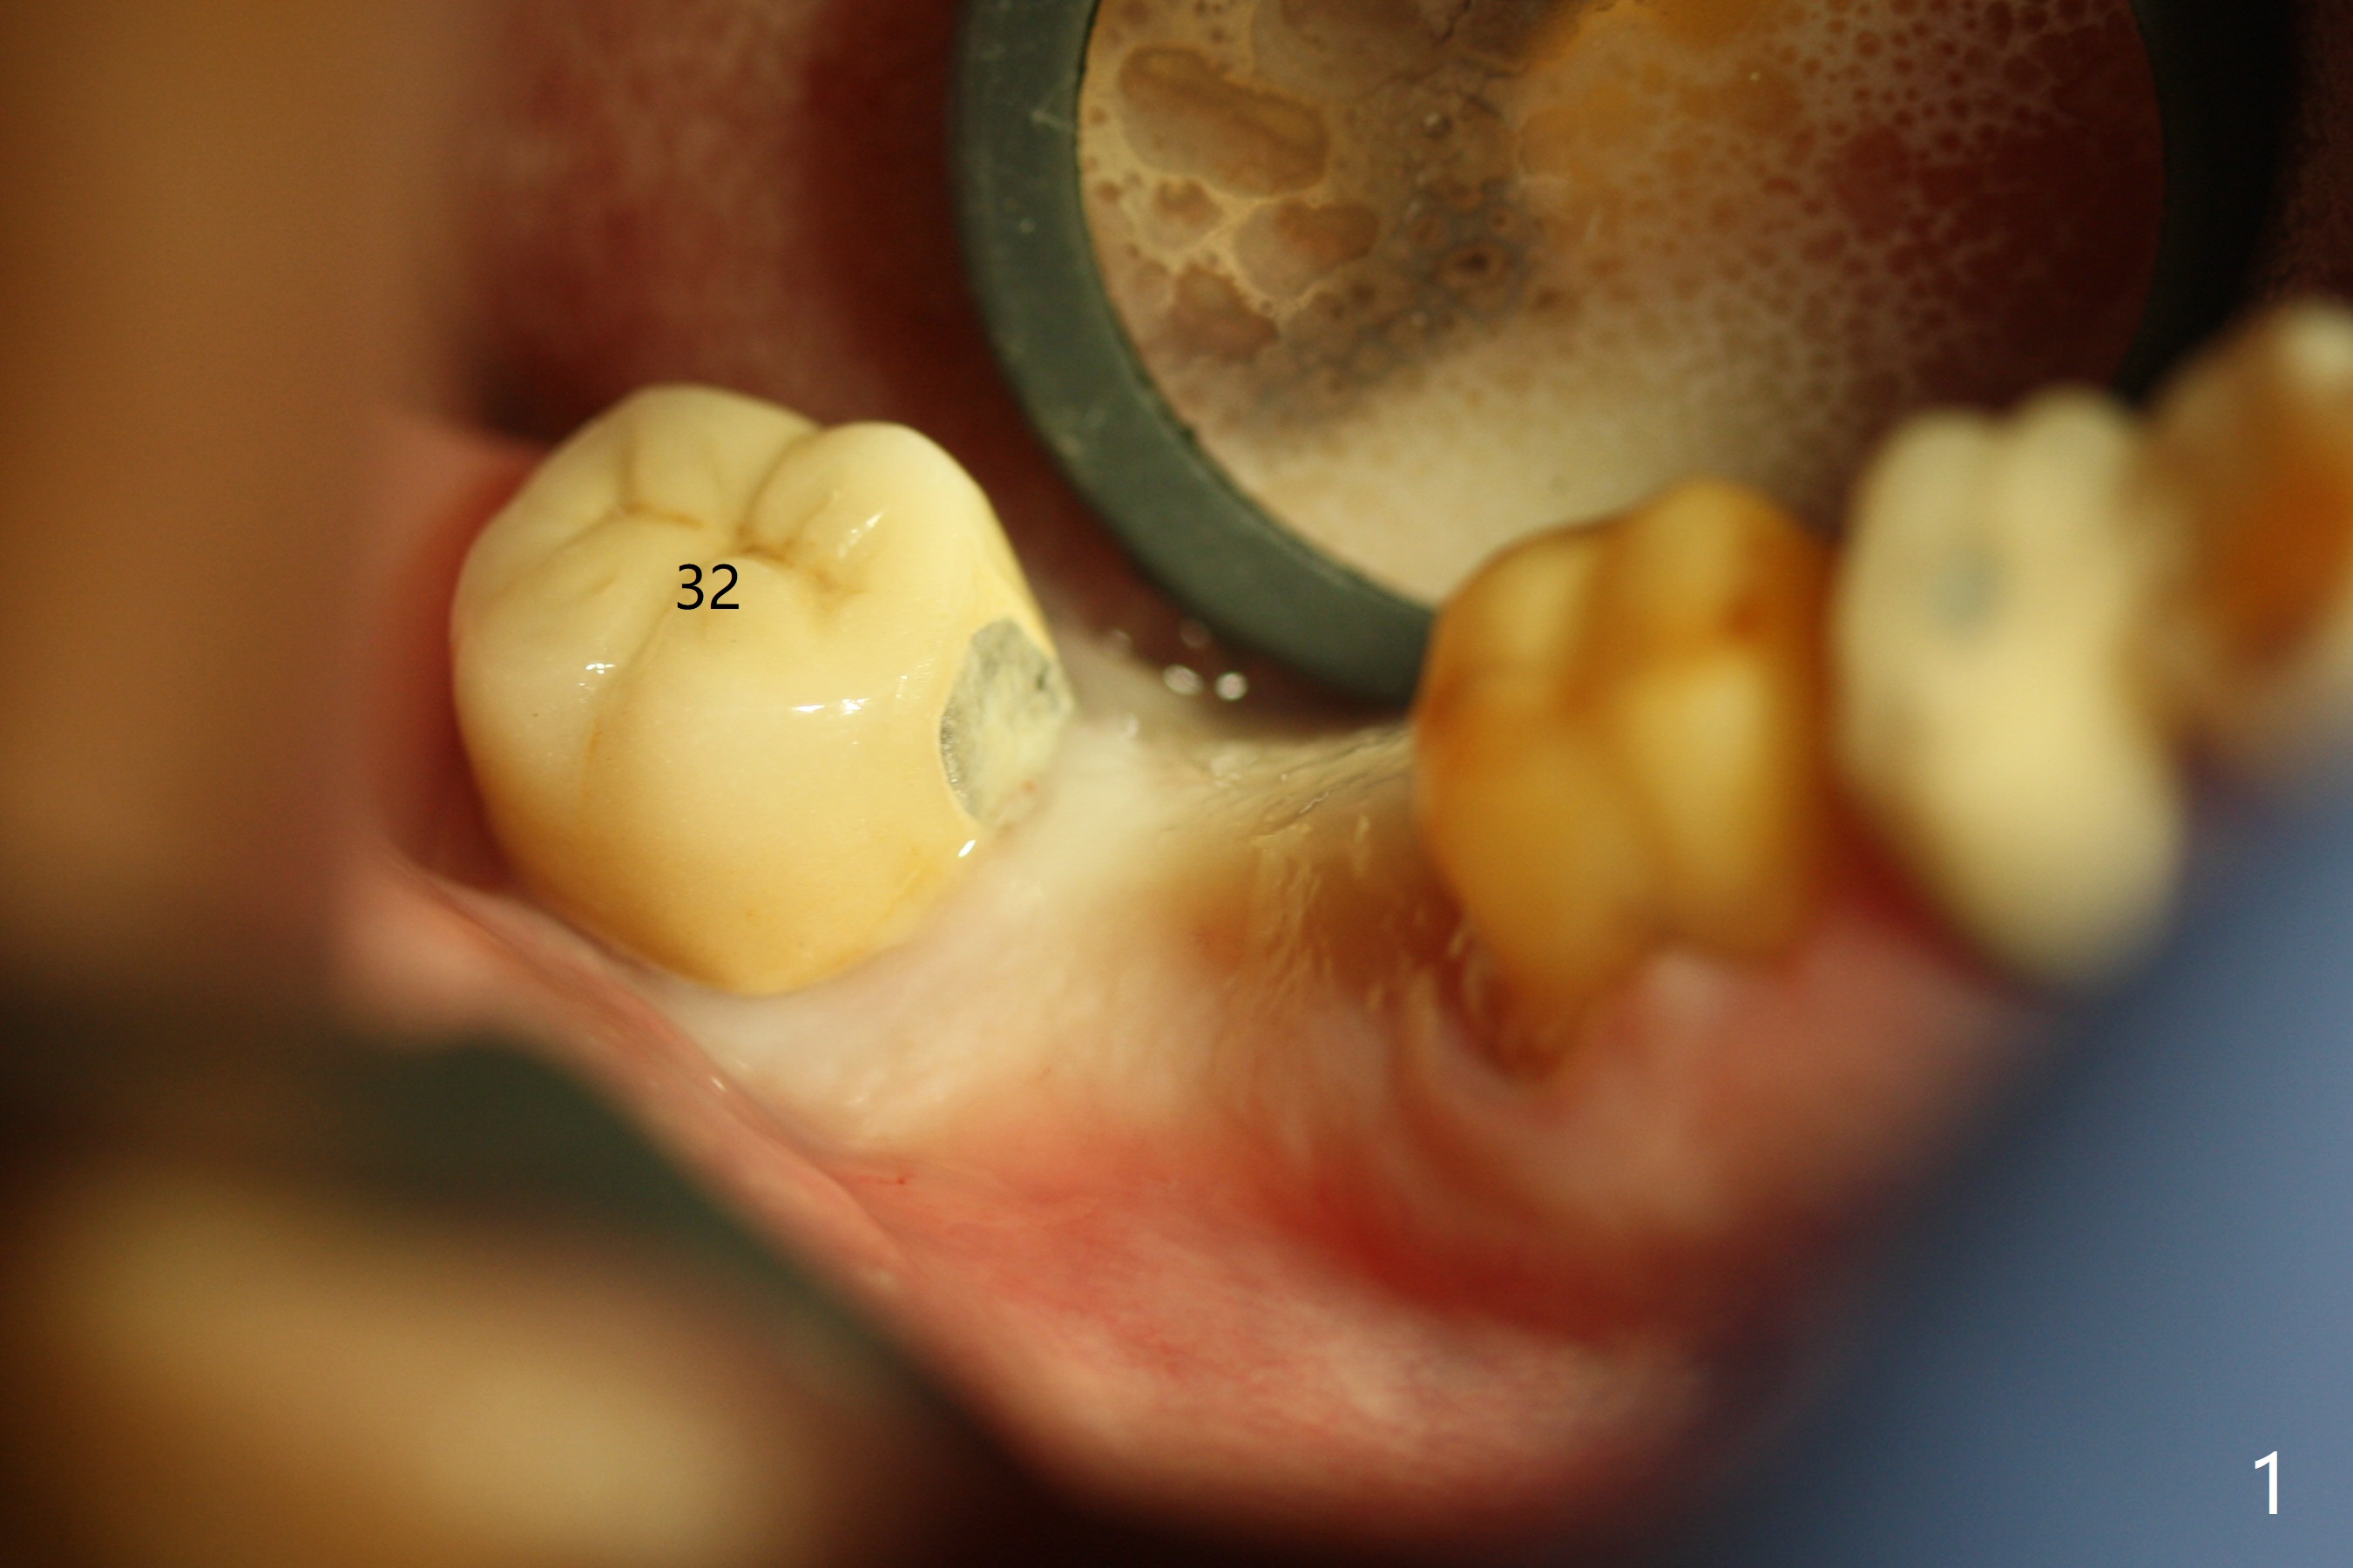

The edentulous ridge at #31 is anesthetized with one carpule of Lidocaine in an infiltration manner for guided surgery (Fig.1,2). In comparison, two or 3 carpules of Lidocaine are required for anesthesia for delayed implant placement without guide. It suggests that guided surgery is associated with less pain. Besides, the implant placed with guide has good trajectory and depth in a timely manner (Fig.3). Since the patient is a heavy bruxer with dislodgement of #30 provisional and #19 abutment screw loosening, a 5.7x4(3) mm cementation abutment is placed immediately so that a splinted provisional is fabricated for #30 and 31 for better retention. However, the gingiva around the implant at #31 is unhealthy 3 months postop (Fig.4). After impression, the provisional at #31 is sectioned without recementation for better oral hygiene. The distal gingival embrasure is large, associated with food impaction (Fig.5). Two years post cementation, the proximal contacts are trimmed (Fig.6 *) for pick up impression for crown repair. The implant and abutment contact is clearly shown with change in X-ray projection (Fig.7). When the new crown with flattened proximal contacts is being seated, it is tight mainly distal. After distal proximal contact adjustment, the crown is recemented without taking out crown/abutment for residual cement removal, because they may be unable to be completely seated because of the flattened larger proximal contacts (hand torque before impression).